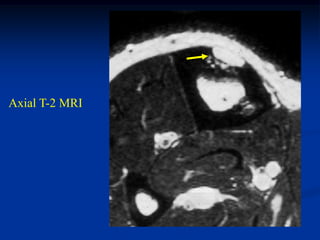

Case #218

58 year female

adamantinoma

proximal tibia

Axial T-2 MRI

Another axial T-2 MRI showing cystic fluid-fluid levels